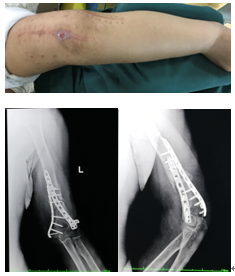

患者于2018年5月25日在工作时不慎从高处坠落,左肘部着地,当即感疼痛,就诊于当地医院,行切开复位内固定术,术后1月患者感前臂麻木,后转至上海医院就诊,后患者左肘前方出现一窦道,伴有渗出(淡黄色液体),行手拇指功能恢复 肌腱转移术,术后康复出院。于2018年10月14日患者左肘部出现一黑色包块,转至我院就诊。

患者入院后,曾晓峰主任及其管床医生进行了详细的询问病史、查体及阅片后,制定了手术方案。于2018年10月18日进行了左肱骨远端感染性骨不连内固定取出清创植骨环形架外固定手术。手术完成的比预期的要顺利,术后予以抗感染等对症治疗,患者手术切口愈合好,干燥无渗出,出院定期复查。

术前:

术后: